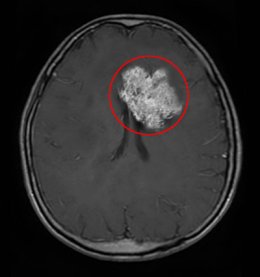

이전에 경련의 병력이 없던 성인의 첫 경련, 지속적으로 심해지면서 메슥거림(오심)과 구토를 동반한 두통, 외상의 병력이 없는 팔다리의 운동 또는 감각저하 등의 증상이 있을 때 의심하며 신경학적 검사 이후 뇌 영상 검사(CT, MR 등)을 시행하게 된다. 조직학적으로 악성도를 다시 4개의 등급으로 분류한다. 조직학적 기준으로는 핵의 비정형성, 유사분열성, 혈관내피세포의 증식, 괴사 등을 기준으로 하며 이러한 기준들이 충족되면 신경교종 중 가장 악성인 4등급의 교모세포종으로 진단내리게 된다. 가장 기본적인 검사는 조영제를 이용한 뇌 컴퓨터 단층촬영이지만 종양이 작거나 주변의 부종이 적을 경우 발견되지 않을 수 있다. 따라서 교모세포종이 의심될 경우에 뇌 자기공명영상(MRI)은 필수적이며 수술 전 및 후에도 재발을 판단하기 위해 매우 중요한 검사이다. 그러나 뇌 자기공명영상만으로 종양의 악성도를 판단하기 어려운 경우이거나 전이성 뇌종양과의 감별을 위해서 양전자 방출 단층촬영(PET)을 시행하기도 하고, 종양의 위치에 따라 뇌 혈관 조영술, 뇌자도검사(MEG) 등 기타의 검사가 추가되기도 한다.

교모세포종의 MRI 소견